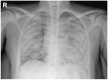

Clinical manifestations accompanying respiratory failure with insidious and rapidly progressive onset are often non-specific. Symptoms such as a cough, dyspnea, and fever are common to a large number of inflammatory, infectious, or neoplastic diseases. During the COVID-19 pandemic it is essential to limit the use of hospital services and inappropriate diagnostic techniques. A particular radiological pattern can orient the clinical and laboratory scenario and guide the diagnostic workup. A 58-year-old woman was admitted to our COVID-19 unit for suspected coronavirus infection. She was complaining of worsening dyspnea, tachycardia, and low grade fever. A chest X-ray showed diffuse, alveolar, and interstitial lung involvement with micronodules tending to coalescence. This radiographic pattern known as "galaxy sign", consistent with diffuse, coalescing nodular miliary pulmonary involvement, simulating a non-specific alveolar opacification of the lungs is typical of a few pneumological differential diagnoses, represented by sarcoidosis, tuberculosis, pneumoconiosis, and metastatic lesions, and virtually excludes an interstitial viral pneumonitis. The use of endoscopic techniques can, in such cases, confirm the clinical suspicion for initiating appropriate targeted therapies.